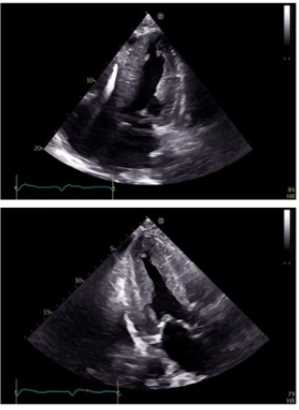

Which diagnosis is most consistent with the findings in these images?

1. Takotsubo cardiomyopathy

2. Apical hypertrophic cardiomyopathy

3. Hypertrophic obstructive cardiomyopathy

4. Restrictive cardiomyopathy from amyloidosis

Answer(s): A

The first image shows a bullseye plot of global longitudinal strain (GLS) with marked reduction in strain values (less negative numbers) most prominently in the apical segments (central red zone), with an overall GLS of -8.2% (normal is about -20%) and a reduced ejection fraction of 41%. This pattern is characteristic of Takotsubo cardiomyopathy, which typically demonstrates regional wall motion abnormalities that predominantly involve the apex and mid segments of the left ventricle with basal sparing.

The 2D echocardiographic images show apical ballooning, a hallmark of Takotsubo cardiomyopathy, where the apex is akinetic or dyskinetic and the basal segments contract normally or hypercontract.

Doppler images show findings consistent with impaired ventricular function.